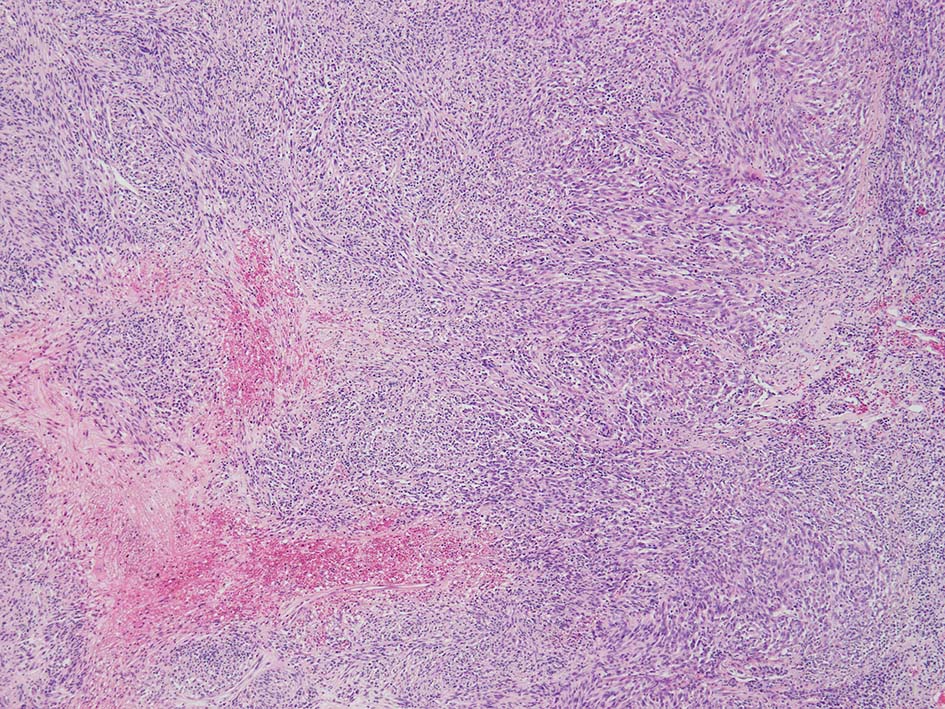

紡錘形異型メラノサイトが著明な間質反応(desmoplasia)を伴い増殖する特殊な色素性病変。*1. desmoplastic neurotropic melanomaは, desmoplastic melanomaのうち神経向性(neurotropism:神経周囲侵襲像)がめだつものでReedら*2が最初に報告した。

いずれも腫瘍細胞の異型性が乏しく, 背景の間質反応がめだつこと, メラニンの存在が目立たないことが特徴である。

病理組織所見*4

再発腫瘤病変の組織像